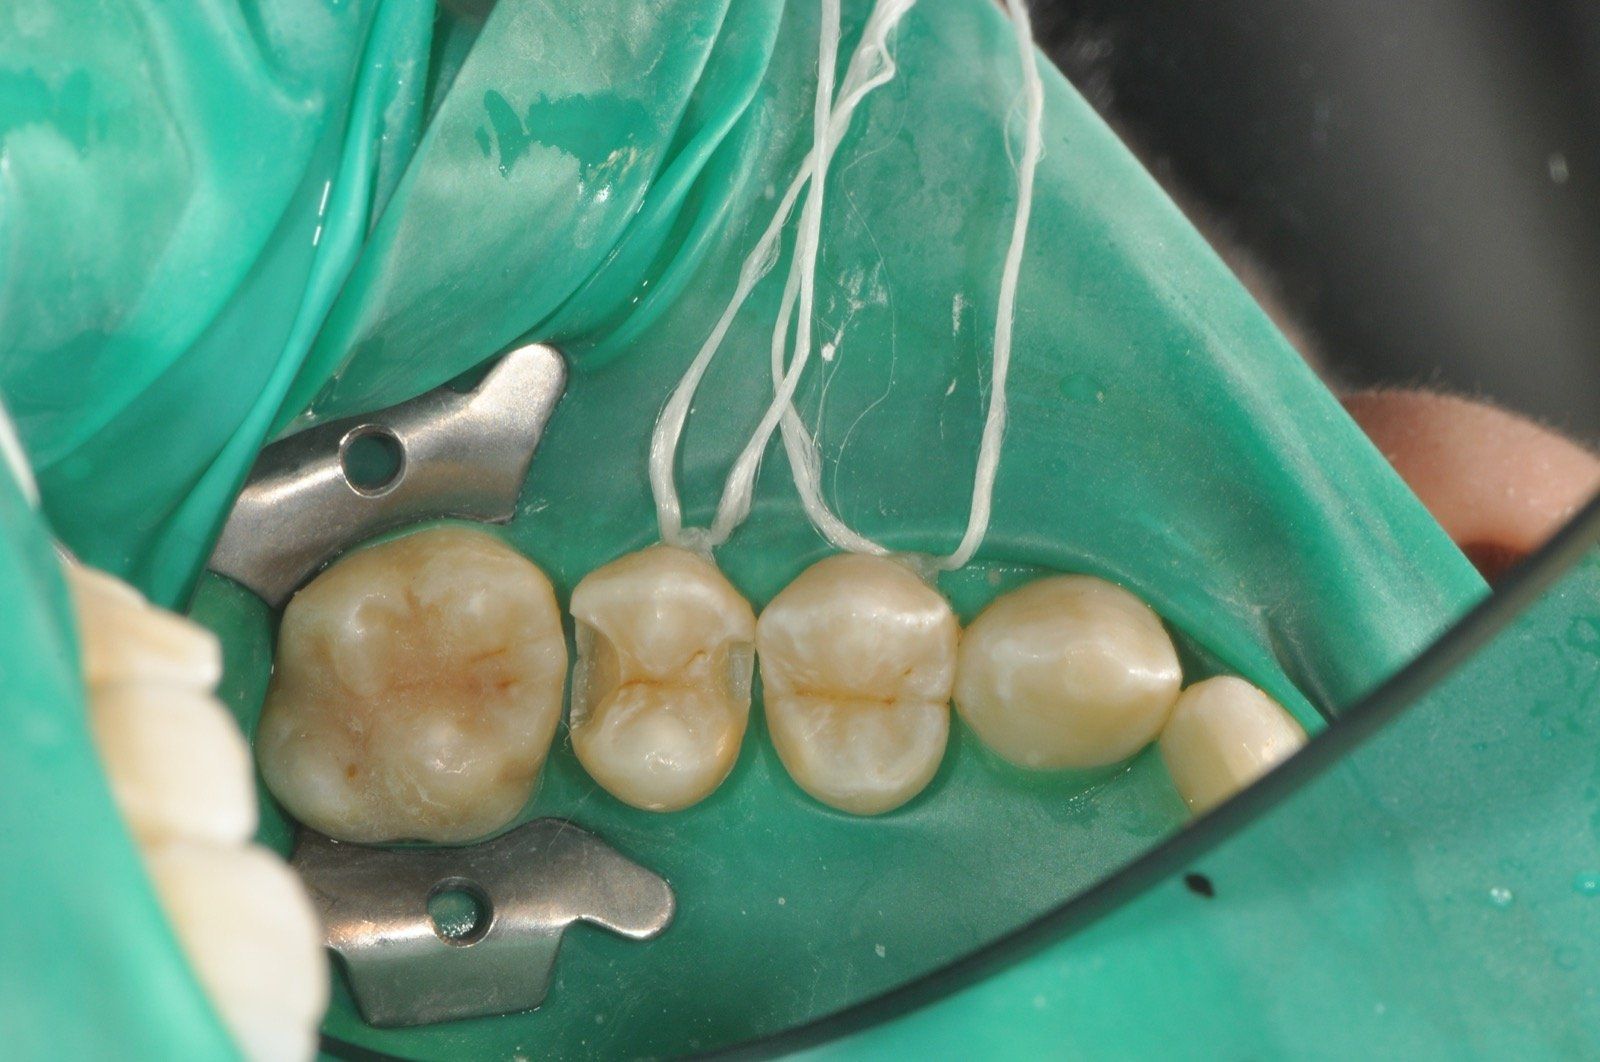

Odontoiatria conservativa

Nella pratica quotidiana mettiamo a disposizione le competenze necessarie abbinate ad una strumentazione all'avanguardia per poter eseguire sedute di endodonzia e di odontoiatria conservativa.

La conservativa è una branca dell'odontoiatria restaurativa che ha come scopo quello di “conservare” l’elemento dentario. Ciò significa che si cercherà, in un dente non eccessivamente compromesso, di evitare la devitalizzazione ove possibile e di restaurare il dente secondo protocolli rigidi che ci garantiscano una longevità della ricostruzione.

Andremo ad effettuare il restauro del dente nella sola parte compromessa dalla carie salvaguardando la sostanza biologica residua, da noi giudicata sana, in modo tale da garantire una ricostruzione di qualità.